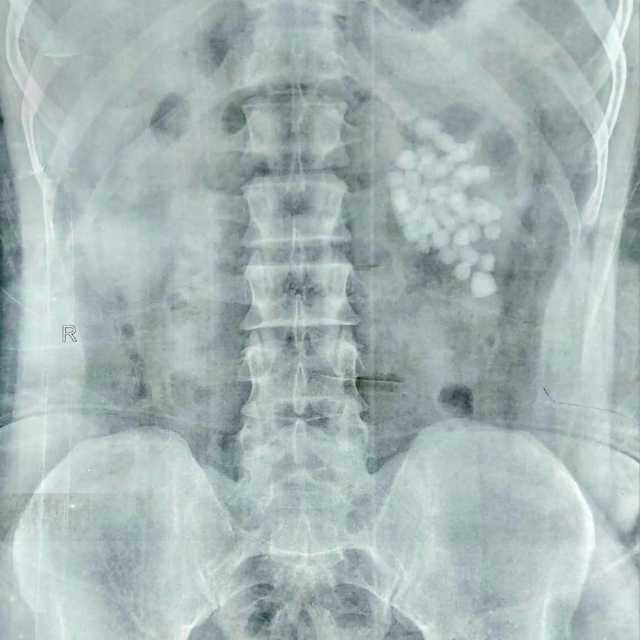

أعلن الدكتور حجاجي منصور، المدير التنفيذي لمستشفيات قنا الجامعية، نجاح فريق طبي متخصص بمستشفى المعبر الجامعي في إجراء عملية دقيقة لاستخراج 58 حصوة من الكلية اليسرى لمريض يبلغ من العمر 40 عامًا، وذلك باستخدام أحدث تقنيات مناظير الكلى المتقدمة.

وأوضح الدكتور مصطفى عبدالرازق، رئيس قسم المسالك البولية بمستشفى قنا الجامعى، بأن المريض وصل إلى المستشفى وهو يعاني من آلام متكررة وارتفاع في نسبة الأملاح، وبعد إجراء الفحوصات اللازمة تبيّن وجود عدد كبير من الحصوات المتجمعة في حوض الكلية اليسرى، مما استدعى التدخل الجراحي الفوري للحفاظ على سلامة الكلية.

وتابع عبدالرازق، وتم تجهيز المريض للعملية وإجراء التخدير العام، ثم بدأ الفريق الطبي العمل بتقنية منظار الكلية عن طريق الجلد، وهي من أحدث الأساليب التي تسمح بإزالة الحصوات الكبيرة والمتعددة بدون فتح جراحي، وتم عمل فتحة جراحية صغيرة لا تتجاوز سنتيمترًا واحدًا للوصول إلى الكلية، ثم تفتيت الحصوات باستخدام تقنيات التفتيت الهوائي والليزر تبعًا لطبيعة كل حصوة.

وأشار رئيس قسم المسالك البولية بمستشفى قنا الجامعى، إلى أن العملية استغرقت ساعتين، تمكن خلالها الفريق الطبي من استخراج الحصوات كاملة مع التأكد من تنظيف حوض الكلية تمامًا لمنع تكرار المشكلة مستقبلًا، كما تم وضع أنبوب تصريف مؤقت لضمان خروج السوائل بشكل آمن بعد العملية، وخرج المريض من غرفة العمليات في حالة مستقرة، بينما تمت متابعة علاماته الحيوية داخل الإفاقة، وسط تحسن ملحوظ في حالته العامة ووظائف الكلى.